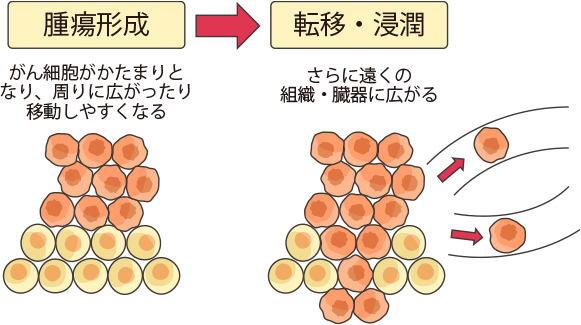

がんはこうして大きくなる

がん細胞が広がる仕組み

がんは、遺伝子が傷ついた異常な細胞(がん細胞)がかたまってできたものです。がん細胞は、増え続けかたまりを作る性質をもっています。

また、がん細胞は、増え続けるだけでなく、周囲に広がったり(浸潤)、他の臓器に移ったり(転移)して新しいがんを作る特徴があります。

さらに、がん細胞は、正常な細胞が必要とする栄養を奪い、身体をどんどん衰弱させる特徴をもっています。